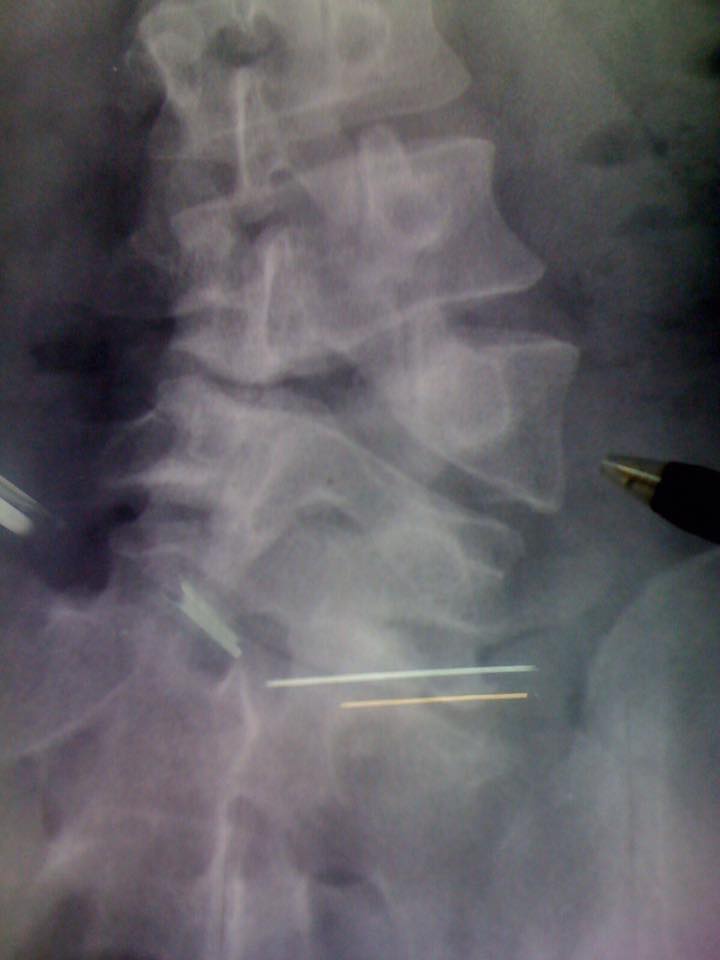

え?

背骨が

無い?

「あー、そういう事ね!背骨が欠けてると

いうか写真の通り奇形があるということね」

背骨が無いんです!にはぶったまげたけど

結構こういう奇形のひとは頻繁にいるんだ。

例えばレントゲンも撮らないでこんな

棘突起を辿って矯正をしたとする。

非常におっそろしい結果が待ってますねきっと。

見つけやすすぎる腰椎の歪み

レントゲンも見せられてもうね、

スゲ~~~!興味深くて。